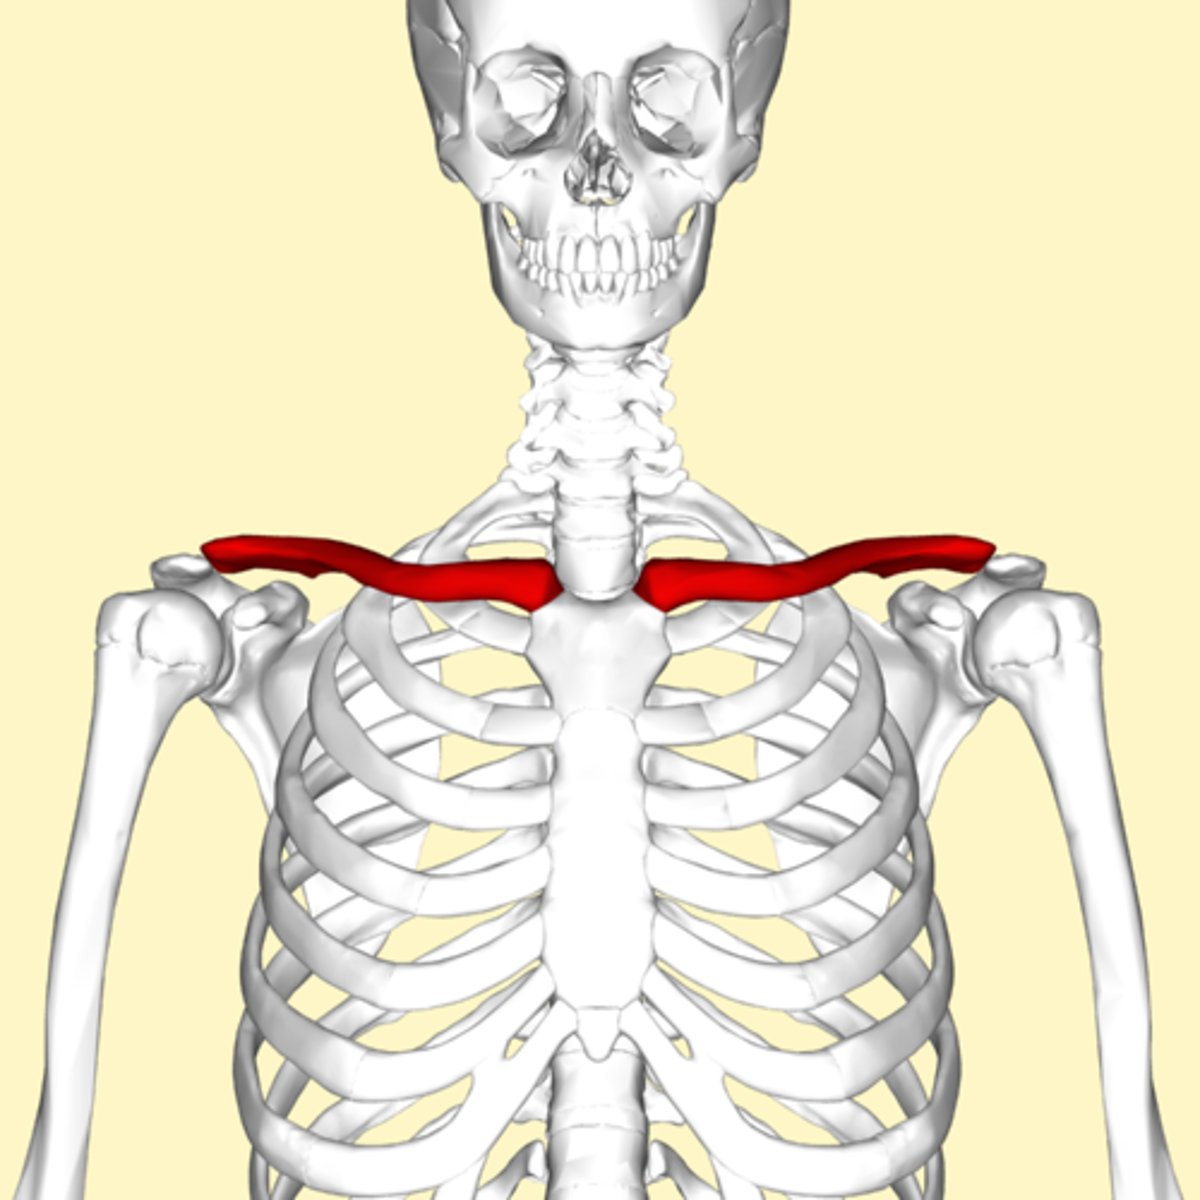

protraction

moving the mandible or clavicle anteriorly

retraction

moving mandible or clavicle posteriorly

Clavicle collarbone